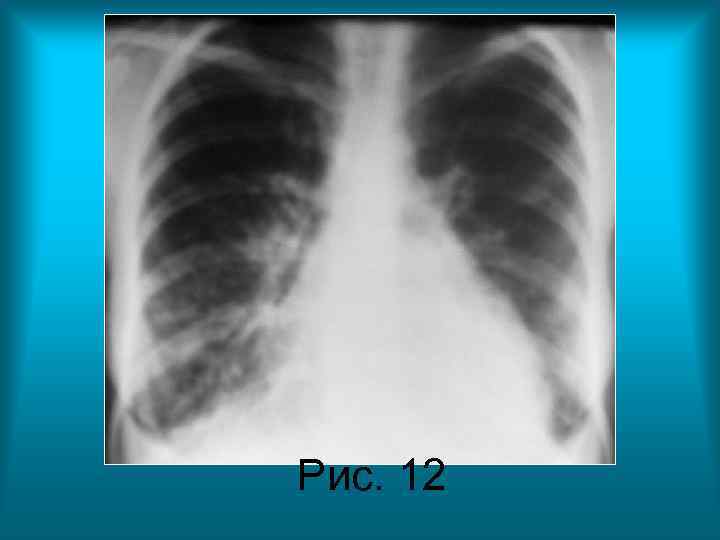

• Пациентка Б. 28 л. Диагноз: Системная красная волчанка. Интерстициальный и альвеолярный отек легких. • Рис. 12. Рентгенограмма органов грудной полости в прямой проекции. Грудная клетка бочкообразной формы. Верхние отделы легочных полей увеличены в размерах за счет повышенной пневматизации, а нижние – находятся в состоянии гиповентиляции. Прозрачность легочных полей снижена за счет обогащения и деформации легочного рисунка, мелкоочаговых теней и утолщения костальной плевры. Реберно- диафрагмальные синусы затемнены, контуры куполов диафрагмы не дифференцируются. Срединная тень расширена в поперечнике, контуры ее нечеткие, неровные.

Рис. 12